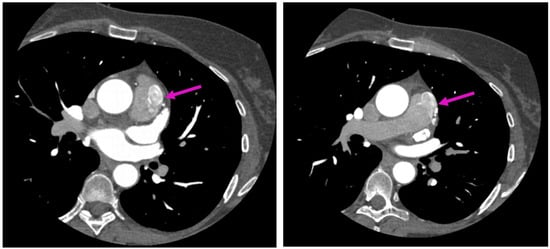

Invasive coronary angiography revealed a small-caliber anomalous tortuous vascular communication (marked with the blue arrow) arising from the proximal segment of the left anterior descending coronary artery (LAD), highly suggestive of a coronary fistula (Figure 1; Videos S2 and S3).

Figure 2. Axial sections of coronary CTA acquisitions—entitled “A picture is worth a thousand words”. show an anomalous tortuous vascular connection with drainage situs in the anterior surface of the pulmonary trunk, fully illustrating diffusion of the resulting contrast blush within the pulmonary trunk, also known as the contrast shunt sign, in a relatively less-opacified pulmonary trunk (pink arrow).